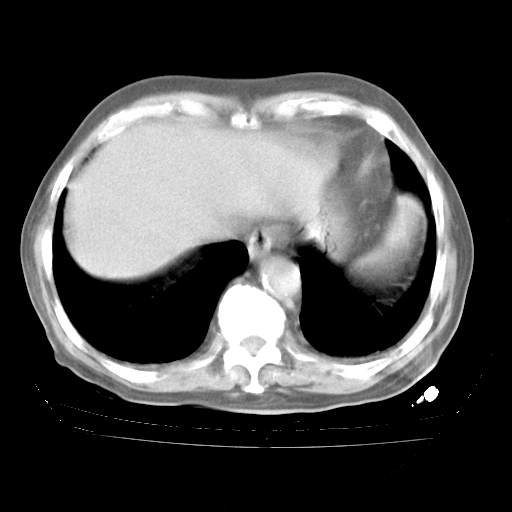

4月28日肺部CT——再次出现类似去年5月9日——磨玻璃样、间有“粟粒样”改变。

4月28日肺部CT